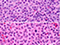

Infectious mononucleosis. Admixed population of cells of varying sizes. In areas where immunoblasts predominated (right) which could be a florid expansions, like large aggregates or sheets of cells with mitotic activity. Spend some time on low power to appreciate the normal architecture, try to find areas with a variety of cell types. Immunoblasts may resemble Reed-Sternberg (RS) cells (inset). [3]